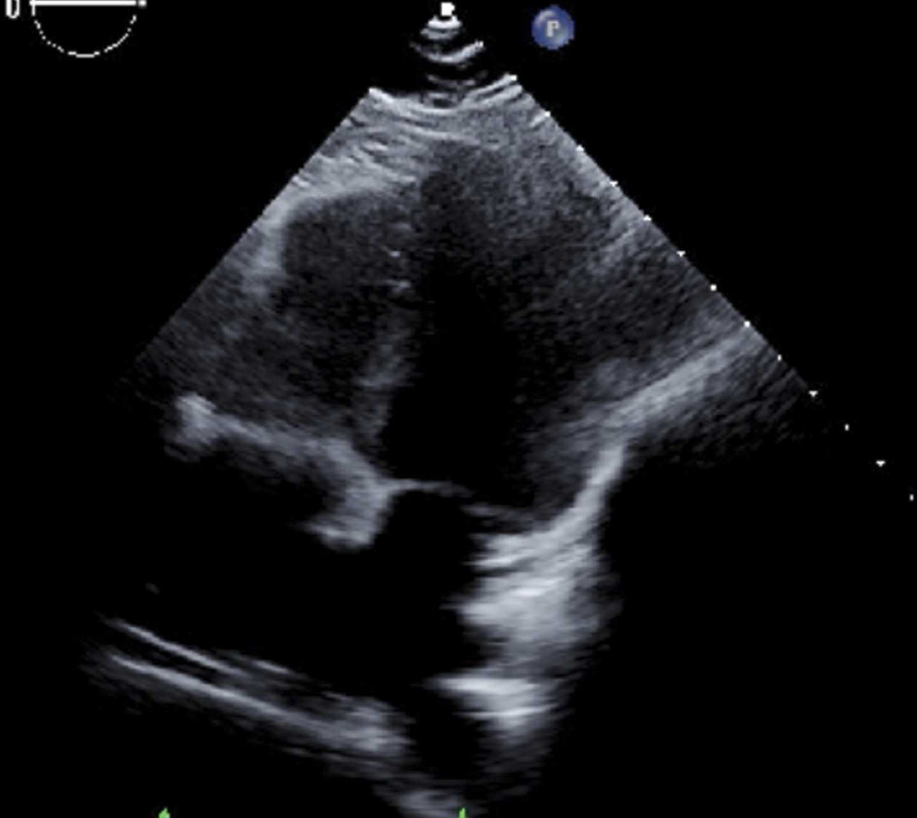

1个月后随访,TTE示心包积液进一步减少(图4),呼吸困难症状完全缓解。

图4 1 个月后复查经胸超声心动图